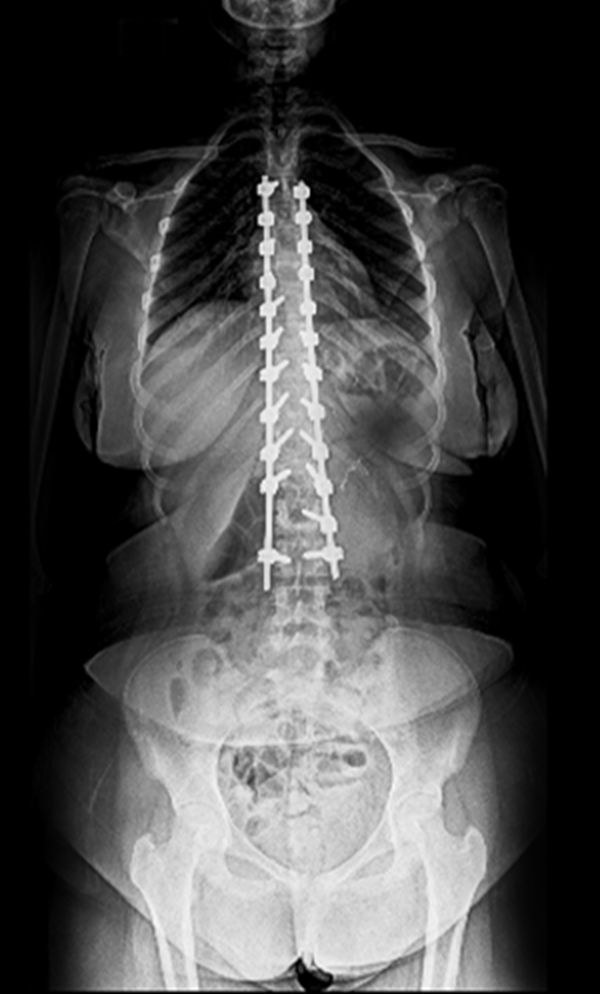

BEYOND RECOVERY : REAL STORIES

Gallery : Before - After